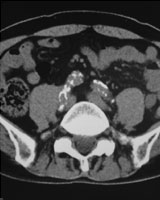

症例1

59歳 女性

【主 訴】

腹痛・体重減少(10kg)

【起始・経過】

平成15年7月より毎食後に腹痛出現。

平成18年5月他院腹部血管造影にて腹部動脈閉塞を認めたが、加療されず。

7月当院受診。

【既往歴】

41歳 子宮筋腫 → 手術

高血圧(+) 糖尿病(−) 喫煙歴(−)

【治療計画】

SMA PTA/stent(Brachial approach)

腹部血管造影検査